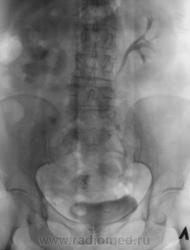

Пациент направлен на внутривенную урографию. Диагноз - "Мочекаменная болезнь?". Врач УЗИ сообщил, что "камни" с обеих сторон. По поводу картины сильно не распространялся.

1. Пациент? Или пациентка? (судя по ширине малого таза и наличия в нем обызествления характерного в большей степени для обызествленного фиброматозного узла);

2.Крупный коралл правой почки и камень лоханки левой почки;

3.Блок правой почки, как следствие МКБ (камни в средней трети правого мочеточника);

4. Отток слева не нарушен;

5.Округлый дефект выполнения в области устья правого мочеточника вполне может быть обьяснен наличием уретероцеле, а тогда станет понятна и причина камнеобразования справа.